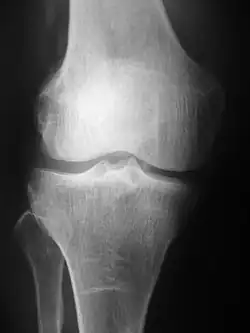

Radiografiile (denumite inițial roentgenografii, numite după descoperitorul de raze X, Wilhelm Conrad Röntgen ) sunt produse prin transmiterea razelor X printr-un pacient. Razele X sunt proiectate prin corp pe un detector; se formează o imagine pe baza căreia razele trec (și sunt detectate) față de cele care sunt absorbite sau împrăștiate la pacient (și astfel nu sunt detectate). Röntgen a descoperit razele X la 8 noiembrie 1895 și a primit primul premiu Nobel de fizică pentru descoperirea lor în 1901.

În radiografia pe ecran de film, un tub cu raze X generează un fascicul de raze X, care este orientat către pacient. Razele X care trec prin pacient sunt filtrate printr-un dispozitiv numit grilă sau filtru de raze X, pentru a reduce împrăștierea și lovește un film nedevelopat, care este ținut strâns într-un ecran cu atomi de fosfor care emit lumină într-o casetă. Filmul este apoi developat chimic și o imagine apare pe film. Radiografia pe ecran este înlocuită cu radiografia pe placă de fosfor, dar mai recent cu radiografia digitală (RD) și imagistica EOS . [3] În cele mai recente două sisteme, senzorii de izolare a razelor X care transformă semnalele generate în informații digitale, care sunt transmise și transformate într-o imagine afișată pe ecranul computerului. În radiografia digitală, senzorii formează o placă, dar în sistemul EOS, care este un sistem de scanare prin sloturi, un senzor liniar scanează vertical pacientul.